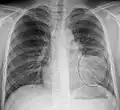

-

Normal AP CXR

Normal lateral CXR -